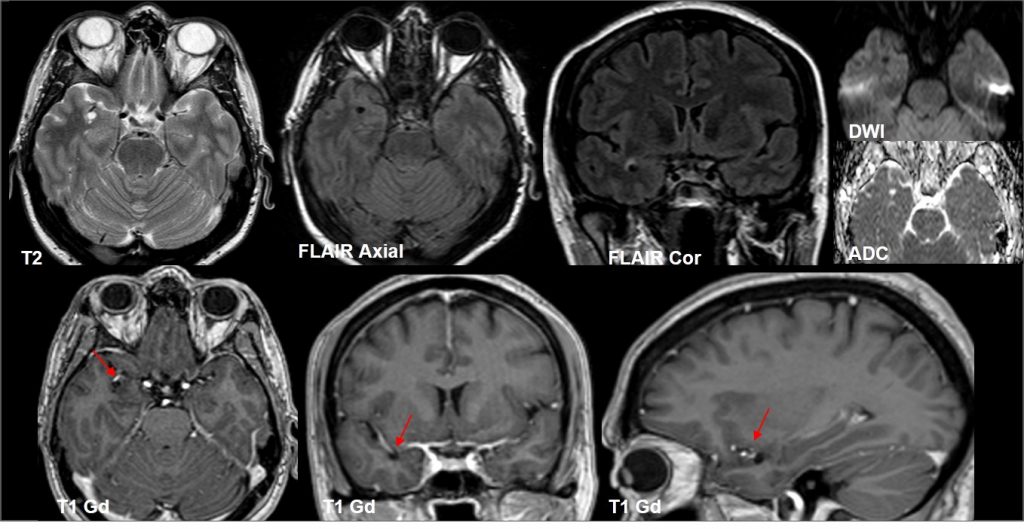

RM cerebral donde se observa lesión de 5 mm en región temporal anterior derecha, próxima a ramas de la ACM derecha (flechas), hiperintensa en T2, hipointensa en T1 y FLAIR, con periferia hiperintensa en FLAIR (punta flecha). Se asocia a pequeño espacio perivascular adyacente (asterisco). No se evidencia realce tras la administración de contraste ni restricción en el estudio de difusión. Control a los 6 y 12 meses, estable.

Lesiones de entre 5 y 15 mm, redondeadas u ovaladas, de señal similar al LCR (hipointensa en T1 e hiperintensa en T2), con estabilidad de su tamaño a través del tiempo. Únicamente se han descrito 2 casos en que la lesión cambió de tamaño, por aumento en uno y por disminución en el otro.

Suelen asociar grado variable de alteración de la señal o edema perilesional en secuencias potenciadas en T2 (~80%), que ocasionalmente puede variar en el tiempo

Suelen estar contacto o próximos con una estructura vascular, que suele ser una rama de la arteria cerebral media.

No realzan con el contraste.

Pueden asociar pequeños espacios perivasculares adyacentes.